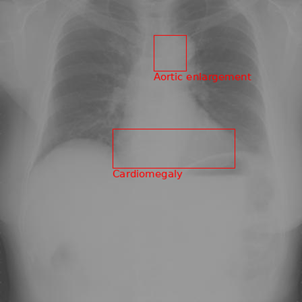

As a qualitative result, Figures 3-5 illustrates an input chest X-ray image along with the disease classification and localization generated by the proposed method using the default prompt with MiniGPT-Med initialization trained with a batch size of 10.

Refer to caption

(a) Other diseases (Test Label)

(b) Other diseases (Model Output)

Figure 3. Qualitative comparison between test labels and model output for other diseases.

Qualitatively, when looking at the example in Figure 3, it has both the test label and the model output for diagnosis as the same, the diagnosis being ’Other Disease’. The model also does a good job of getting some of the correct local labels. There is an aortic enlargement in both the reference and model output, but just barely overlap with one another. Instead of predicting calcification, the model predicts cardiomegaly. Overall, this example comparison is a strong showing for what the model is capable of albeit on a simple (only two abnormalities) data point.